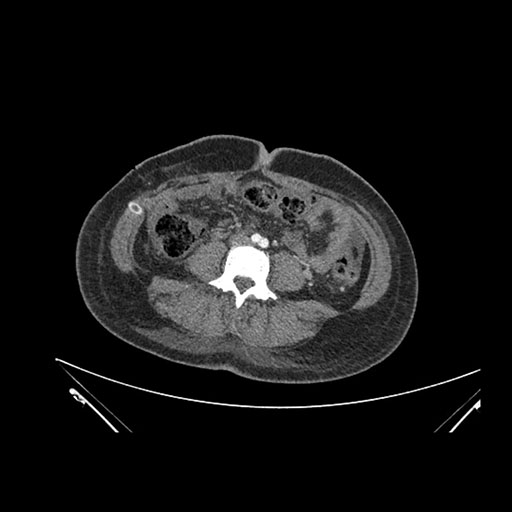

Imaging Analysis

Look through the patient's CT scan to identify any areas of concern for the necessary procedure.

Based on initial findings, which issue(s) would you be most concerned about?